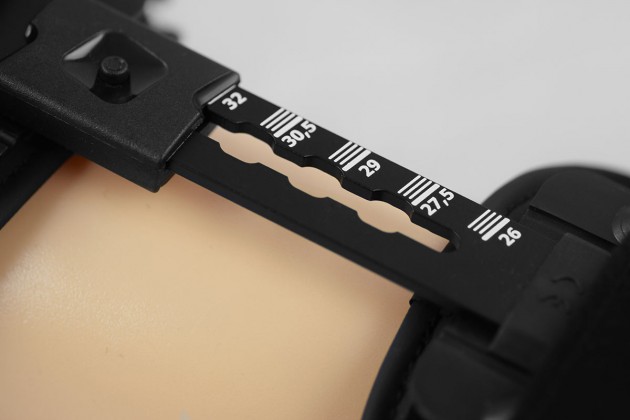

Dodatkowo, szyny posiadają niezależną regulację długości. Zmiana długości części udowej ortezy odbywa się przy użyciu innowacyjnego bezobsługowego mechanizmu press-slide. Regulacja szyn jest bardzo prosta i polega na wciśnięciu przycisku znajdującego się na powierzchni regulatora i wysunięciu szyny na pożądaną długość.